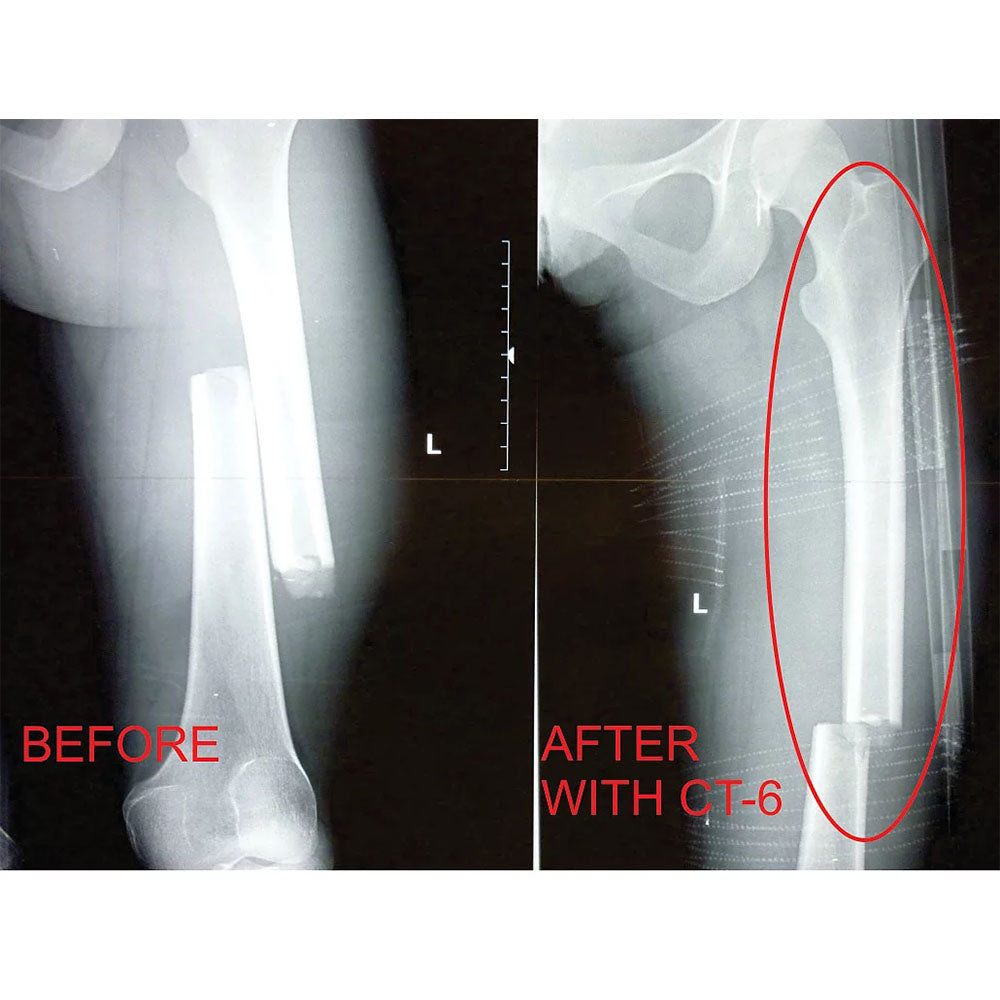

The CT-EMS Bilateral Leg Traction Splint was designed for Pre Hospital Care and Patient transport of patients with two broken legs. This kit includes 2 splints that allow for individual amounts of traction to be applied to both legs. These CT-EMS splints help relieve patient pain and prevent further damage to surrounding muscle and tissue while reducing the risk of death caused by severed arteries.

The CT-EMS is made of carbon tubing which snaps together via an internal bungee. Traction is achieved with a 4 to1 purchase system using a small line to apply tension. This method results in a very precise and delicate form or traction that is also powerful enough to be effective on extra large adults. The CT-EMS is extremely compact, light and strong.

- Effective: Four to one pulley system for efficient, easily adjustable traction.